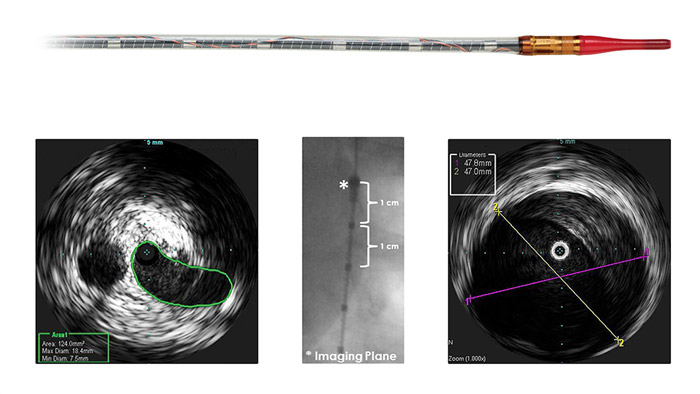

Наши катетеры для визуализации периферических сосудов помогают оценить поражение и морфологию пораженного участка, включая наличие кальция и тромба. ВСУЗИ также используется для выбора стента подходящих размеров и подтверждения результатов лечения

Visions PV (0,035") Цифровой катетер для ВСУЗИ Visions PV (0,035") обеспечивает визуализацию периферических артерий и вен в режиме реального времени для повышения эффективнности проводимого вмешательства.